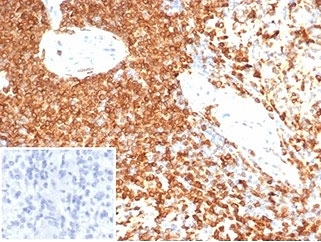

IHC staining of FFPE human spleen tissue with CD74 antibody (clone CLIP/7193) at 2ug/ml. Negative control inset: PBS used instead of primary antibody to control for secondary Ab binding. HIER: boil tissue sections in pH 9 10mM Tris with 1mM EDTA for 20 min and allow to cool before testing.

IHC staining of FFPE human spleen tissue with CD74 antibody (clone CLIP/7193) at 2ug/ml. HIER: boil tissue sections in pH 9 10mM Tris with 1mM EDTA for 20 min and allow to cool before testing.